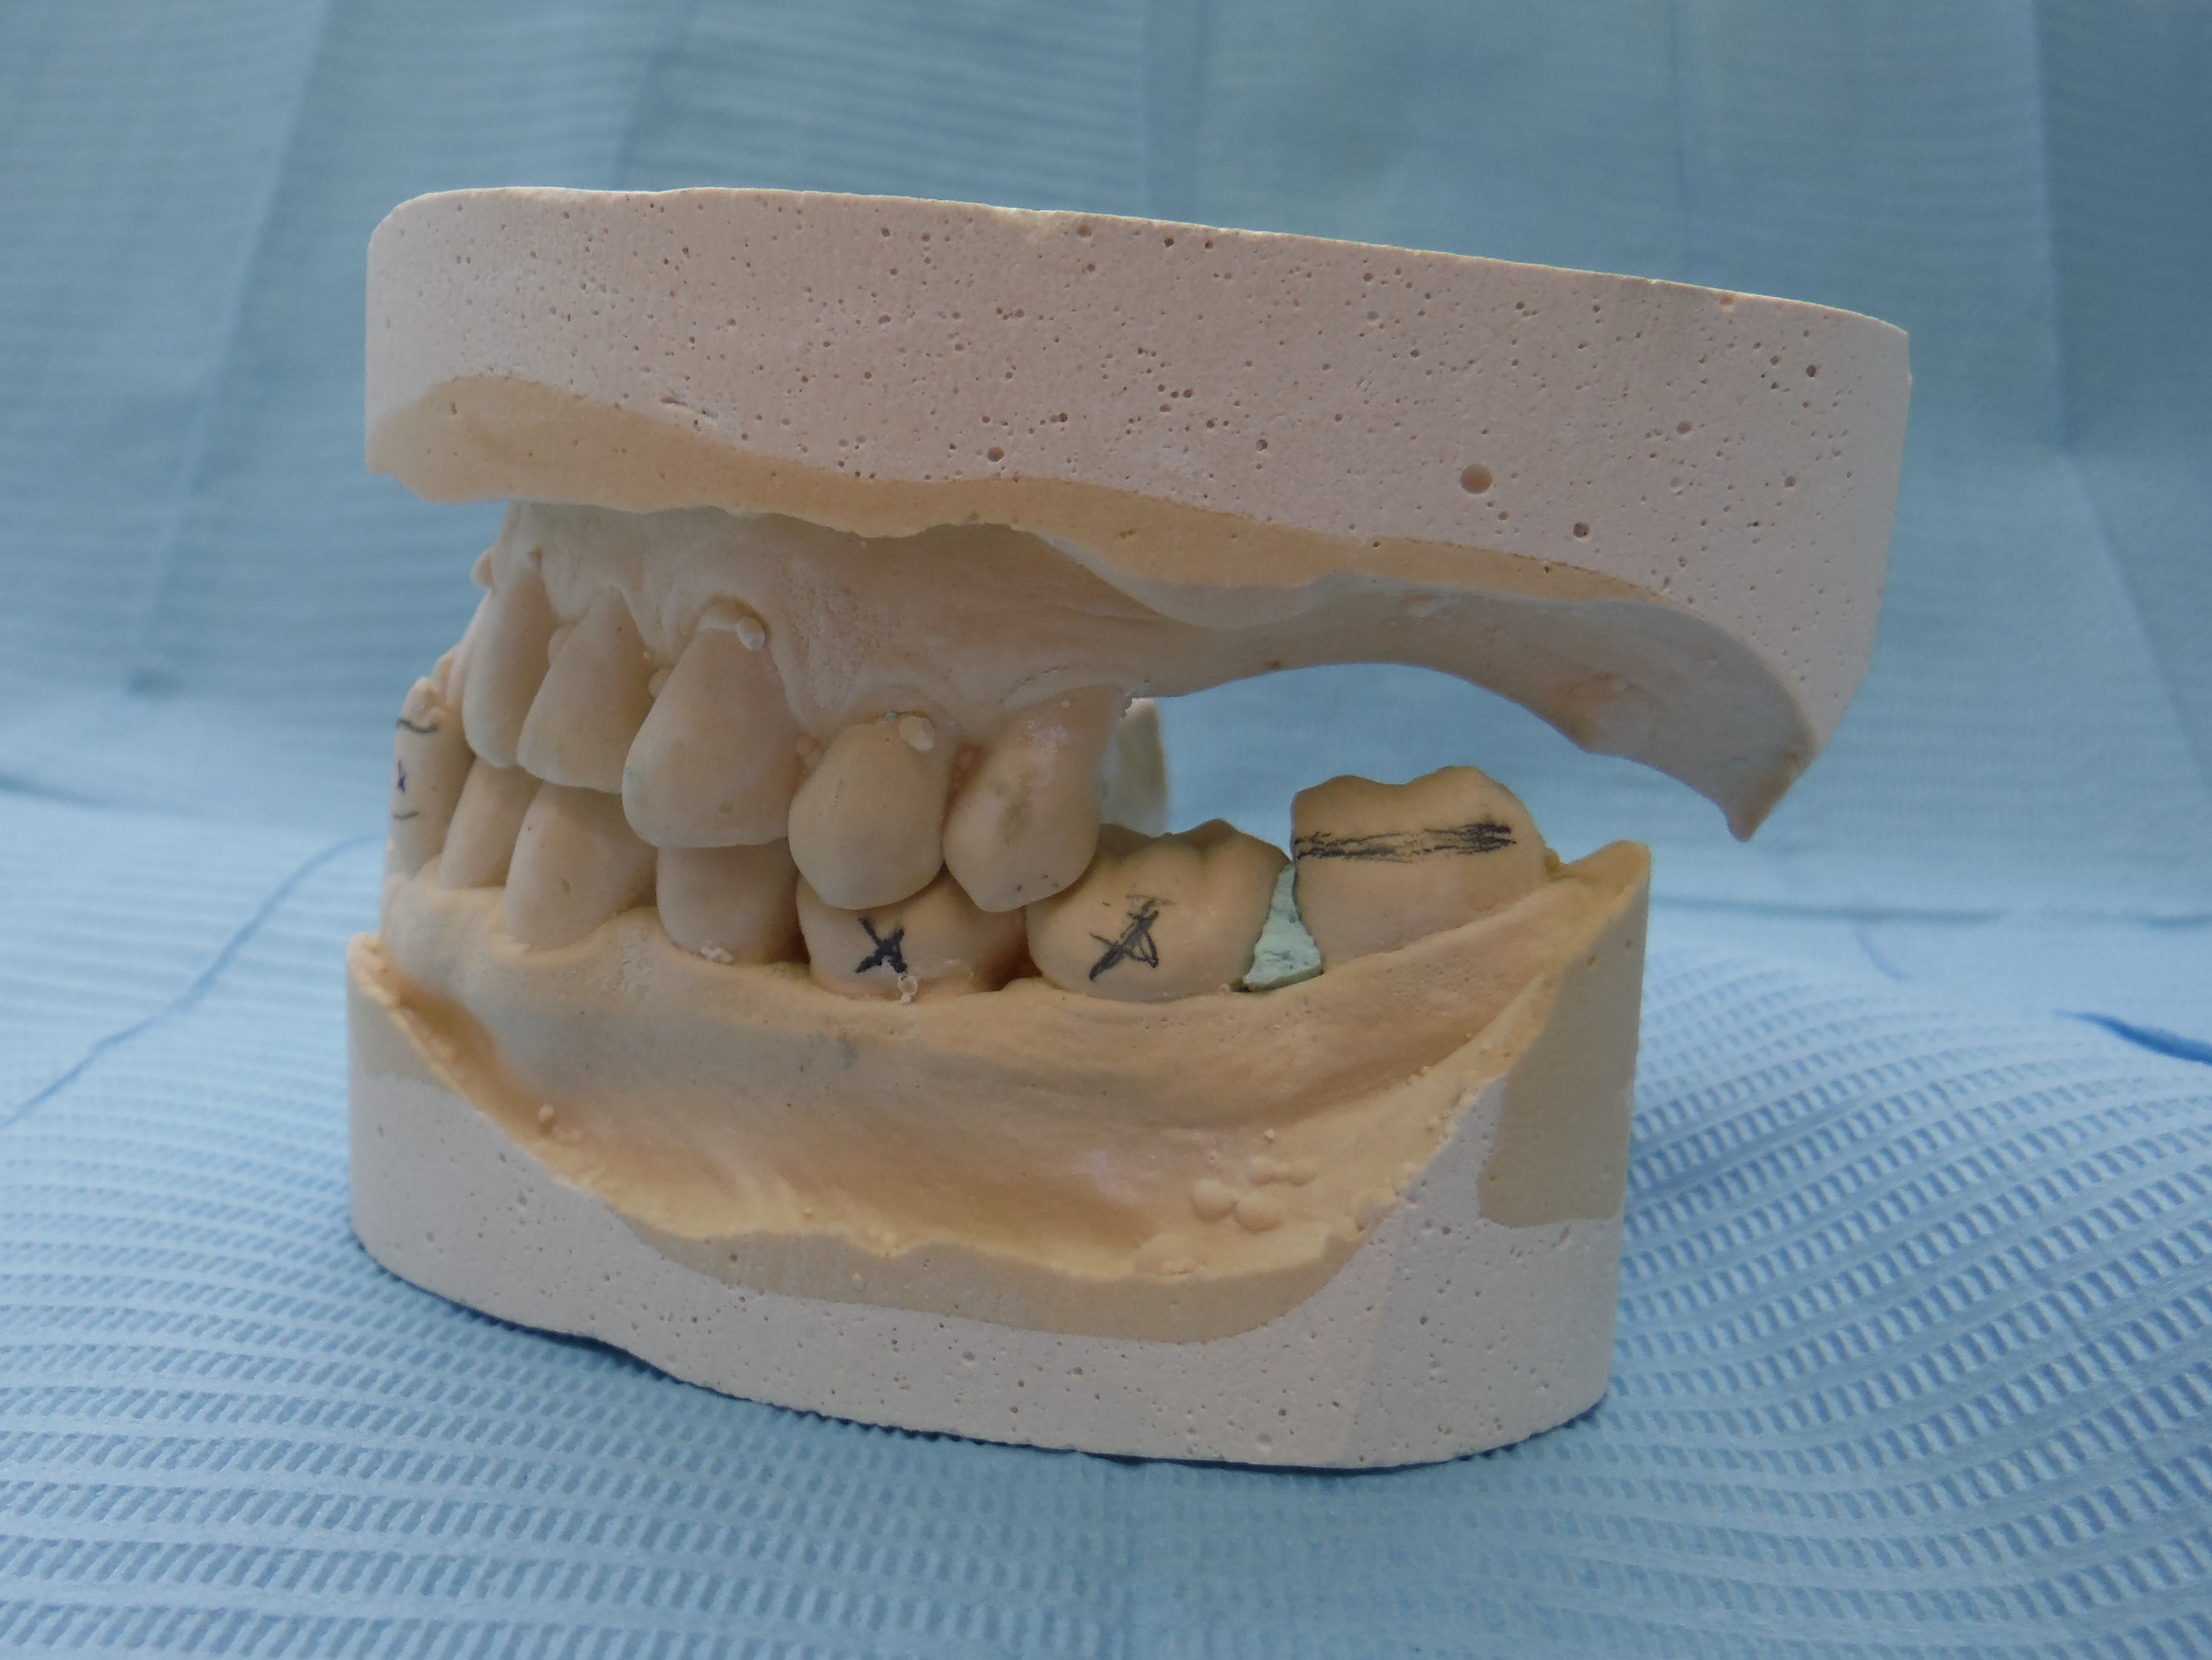

Je "te" marquerai les surfaces d'usures, il y en a.

sans commentaire.

Ah si! 64 ans... et 41, 31 HS...

Lui 59 ans, 41 HS, c'est la semaine!!! les photos ne sont pas tops :-(